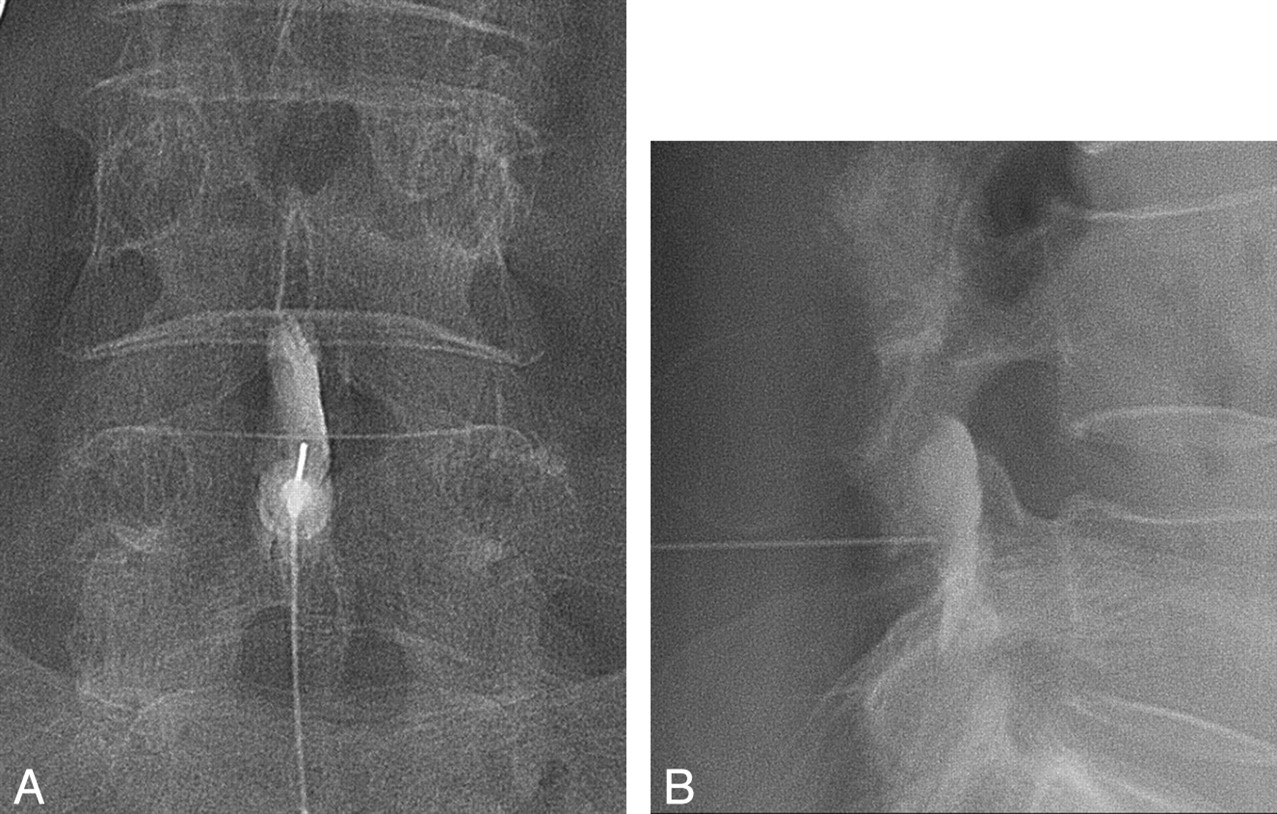

A lumbar interlaminar ESI was performed under fluoroscopic guidance. The level of injection was mostly L4–5, but L3–4 or L5-S1 was also chosen according to the level of abnormal disk or accessibility during the procedure. For multiple levels of disk disease, L4–5 was usually targeted first because most patients had LBP around L4–5 on physical examination. However, this could be changed according to the accessibility. All interlaminar ESI procedures were performed by 1 of 3 radiologists who have experience with >1000 ESI procedures. The uniplanar digital subtraction angiography unit (Intergris Allura Xper FD 20; Philips Healthcare, Best, the Netherlands) was used. With patients in the prone position and under sterile preparation, a 22-ga spinal needle was advanced into the posterior epidural space through the interlaminar space with intermittent injection of contrast agent (Omnipaque 300 [iohexol, 300 mg iodine per mL]; Amersham Health, Princeton, New Jersey) until the contrast agent smoothly spread into the lumbar epidural space (Fig 2). Then, a mixture of 40 mg triamcinolone acetonide suspension (40 mg per milliliter; Tamceton, Hanall Pharmaceutical, Seoul, Korea) and 1.5 mL of normal saline and a mixture of 1 mL of bupivacaine hydrochloride (0.5 mL/0.5%, Marcaine Spinal 0.5% Heavy; AstraZeneca, Westborough, Massachusetts) and 0.5 mL of normal saline were injected into the epidural space. The steroid mixture was injected first, and the anesthetic mixture was injected sequentially.

A 70-year-old woman received an interlaminar ESI. A 22-ga spinal needle was advanced into the posterior epidural space through the interlaminar space with intermittent injection of contrast agent until the contrast agent smoothly spread into the lumbar epidural space on anterior-posterior view (A) and lateral view (B). Then, a mixture of triamcinolone acetonide (Tamceton) and bupivacaine hydrochloride (Marcaine Spinal 0.5% Heavy) was injected into the epidural space.